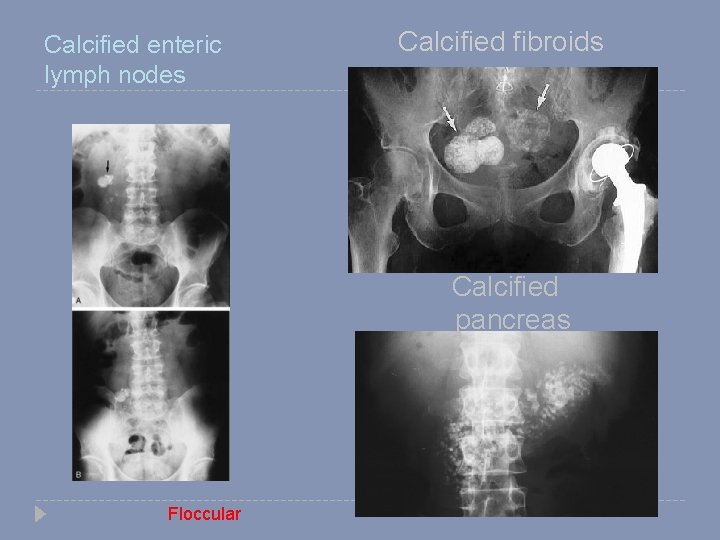

Calcified enteric lymph nodes Calcified fibroids Calcified pancreas Floccular